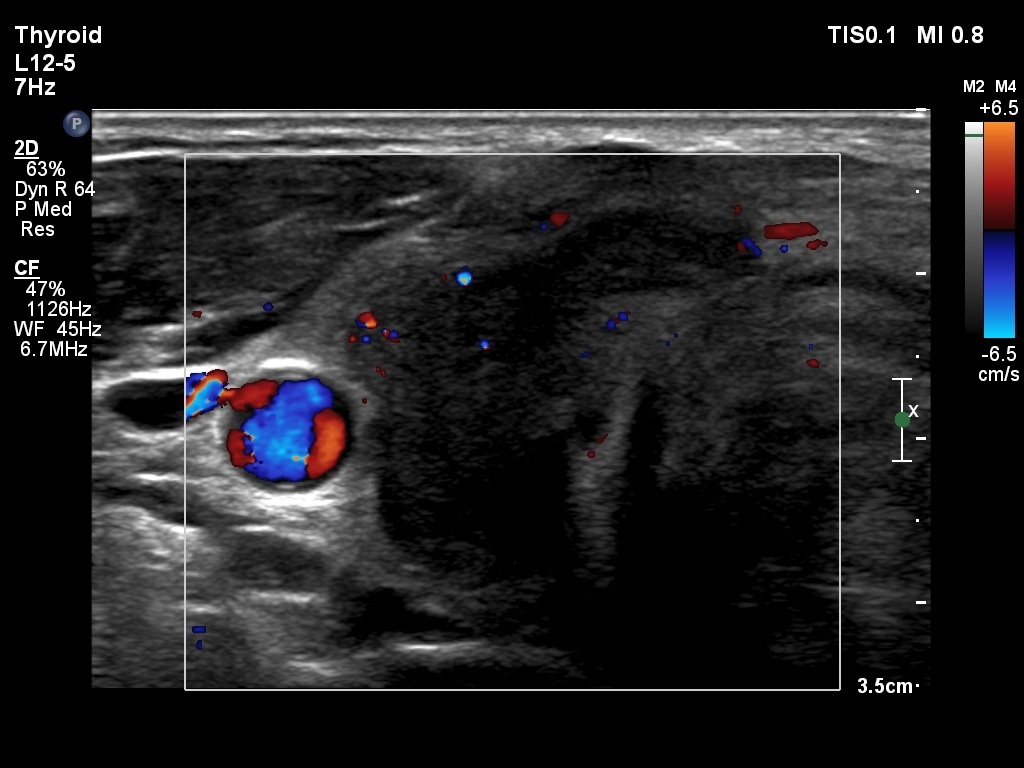

First examination (1st to 3rd rows of images):

Ultrasonography: Both lobes presented hypoechogenic ill-defined areas. The echogenicity index was 80% in the right lobe while 20% in the left thyroid. The vascularization was significantly decreased.

Elastography demonstrated hard areas according to the hypoechogenic field in the left lobe while almost the entire right lobe proved to be hard.Cytological diagnosis: subacute, granulomatous de Quervain's thyroiditis.